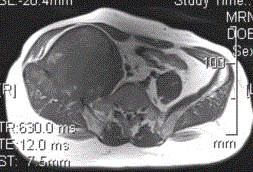

患者男,28岁,右下腹及臀部疼痛5个月余。查体:右髂骨外后侧压痛,右下腹可触及一软组织包块,质韧,固定。行骨盆正位CR、骨盆CT及MR扫描见下图。...

问题 患者男,28岁,右下腹及臀部疼痛5个月余。查体:右髂骨外后侧压痛,右下腹可触及一软组织包块,质韧,固定。行骨盆正位CR、骨盆CT及MR扫描见下图。 关于病变发生的部位,叙述正确的是

选项 A.右髂骨皮质部,累及右侧腰大肌 B.右髂骨髓质部,累及右髂骨皮质及右侧腰大肌 C.右侧腰大肌,累及右髂骨 D.盲肠,累及右髂骨 E.末段回肠,累及右髂骨

答案 B